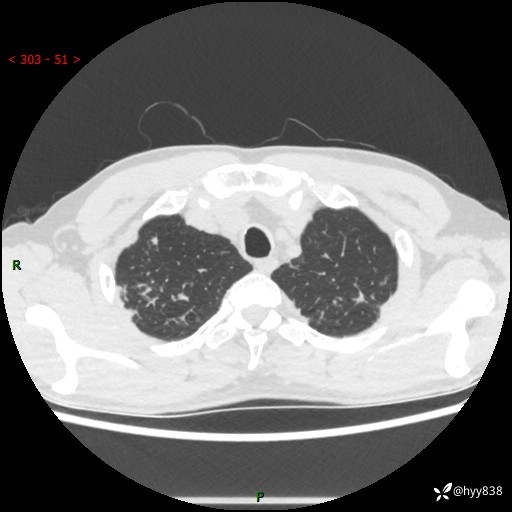

中年男性,咳嗽咳痰1月余。细看:肺、肺门、气管,貌似都有问题---(有结果)

现病史:患者于1个月前受凉后出现间断性咳嗽,伴白色泡沫样痰,无发热寒战、咯血、胸痛胸闷、恶心呕吐、呼吸困难等特殊不适,起初未予特殊处理,后患者就诊当地中医医院,查胸部CT提示支气管炎并双肺感染性病变,经抗感染(哌拉西林舒巴坦),止咳化痰(溴己新、三拗片)等治疗后,患者自诉咳嗽咳痰症状较前缓解,未诉发热等其他特殊不适,近期复查CT提示“肺部感染灶未见消退,双侧肺门增大,双肺散在小结节”,今为求进一步诊治,前来我院就诊,门诊以“肺部感染”收住入院。 患者自起病来精神、食欲、睡眠尚可,大小便正常,体力、体重无明显变化。

胸部CT平扫+增强(两期)